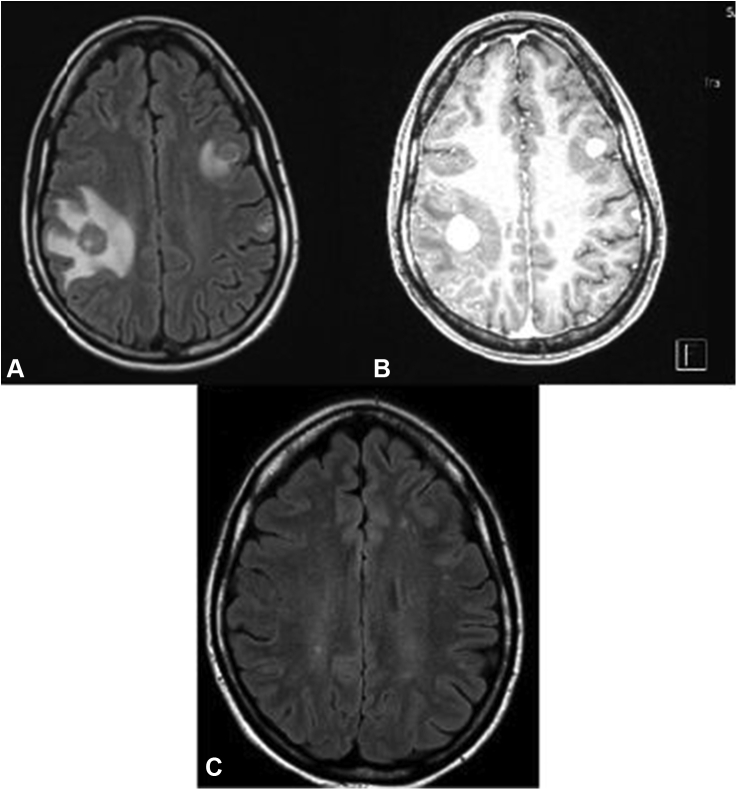

A 27-year-old woman presented after a tonic-clonic seizure. Result of brain magnetic resonance imaging revealed multiple ring-enhancing lesions, and results of computed tomography of the chest and abdomen noted a 2 cm by 1.1 cm left lower lobe lung mass and mediastinal lymphadenopathy (Figs. 1A–C and 2A and B). Result of computed tomography-guided biopsy of a mediastinal lymph node with fluorescence in situ hybridization testing confirmed ALK-rearranged adenocarcinoma, with programmed death-ligand 1 at 35%, and no additional actionable mutations on OnkoSight next-generation sequencing assessment. She underwent stereotactic radiosurgery to the brain metastases, and alectinib 300 mg twice daily was initiated.

Figure 1.

(A) MRI brain T2 flair at the time of diagnosis. (B) MRI brain with contrast at the time of diagnosis. (C) MRI brain with contrast 4.5 years after diagnosis. MRI, magnetic resonance imaging.

The patient has been on alectinib for more than 4 years with isolated progression of disease in the brain on one occasion, approximately three years after therapy initiation, which occurred three months after delivery of her second child. At the time of central nervous system progression, alectinib was increased from 300 mg twice daily to 600 mg twice daily, and the patient underwent additional stereotactic radiosurgery with an objective response to treatment (Fig. 1).